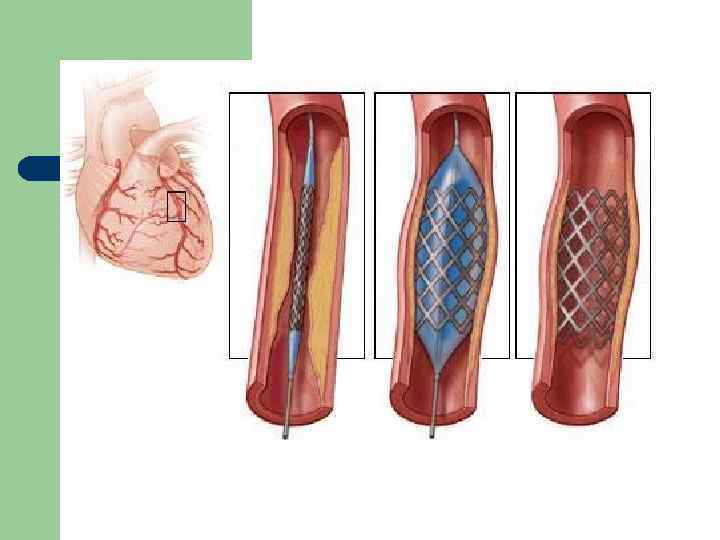

Хиругические методы лечения ИБС l l АКШ: при стенозе ствола ЛКА более чем на 50% или устьевых стенозах ПНА и ОА, при проксимальных стенозах 3 -х основных артерий, при одно- или двухсосудистом поражении с тяжёлым проксимальным стенозом ПНА, при многососудистом поражении с дисфункцией ЛЖ и/или СД. ТБКА (ЧТКА)

Проблема: рестеноз в стенте (гиперплазия неоинтимы) l l l Хуже лечится (отсутствие эффекта при непокрытых металлических стентах – до 45%, при стентах с лекарст. покрытием – 4 -12%). Что делать? Внутристентовая баллонная ангиопластика, рестентирование (стент в стент), брахитерапия, лазерная ангиопластика, ротационная атероэктомия. Наиболее рекомендуемы: имплантация стента с лекарст. покрытием (Cyfer), повтор. ЧТКА баллоном, покрытым цитостатиком паклитакселем, биодеградирующие стенты.